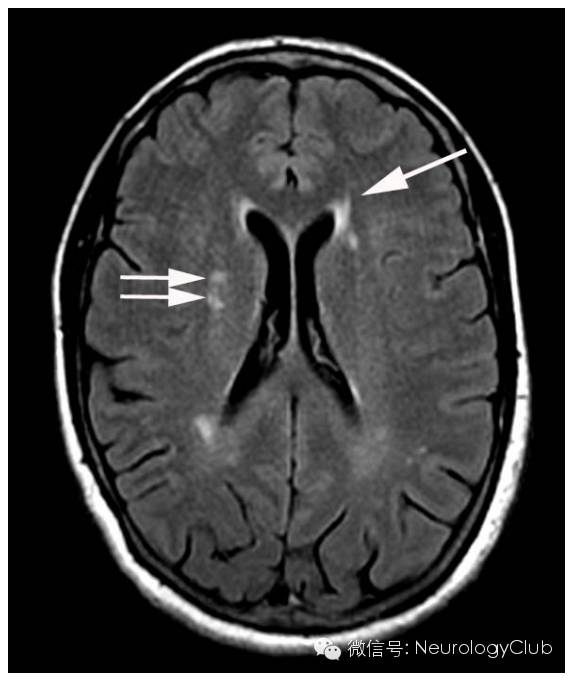

(FLAIR示脑室旁[箭]和皮质下深部单独散在的白质[双箭头]高信号。